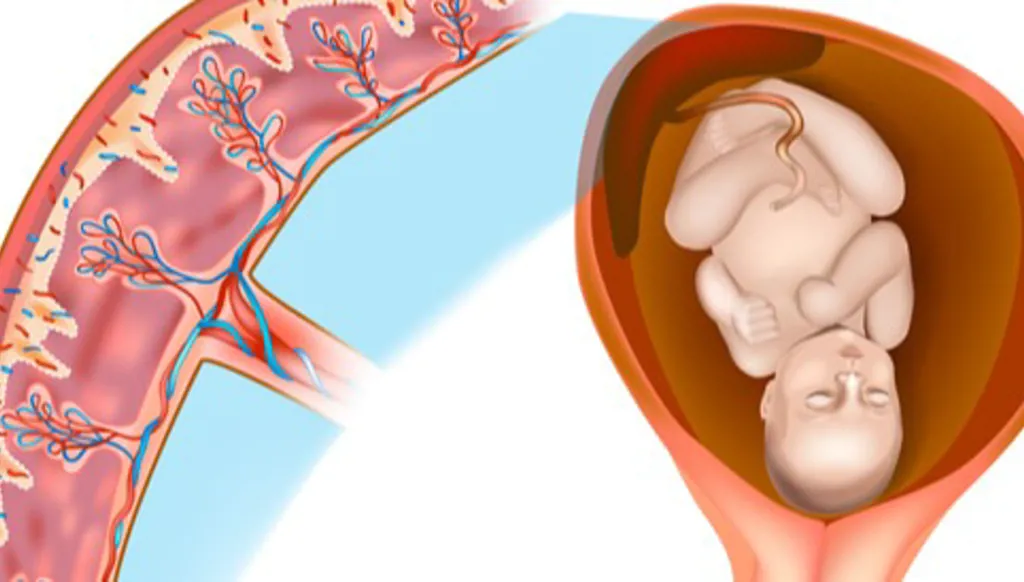

وتحدث هذه الحالة، التي تعرف باسم طيف المشيمة الملتصقة، عندما تلتصق المشيمة بعمق شديد بجدار الرحم ولا تنفصل بعد الولادة، مما يؤدي إلى نزيف حاد بعد الولادة وأحياناً إلى استئصال الرحم وحتى الوفاة.